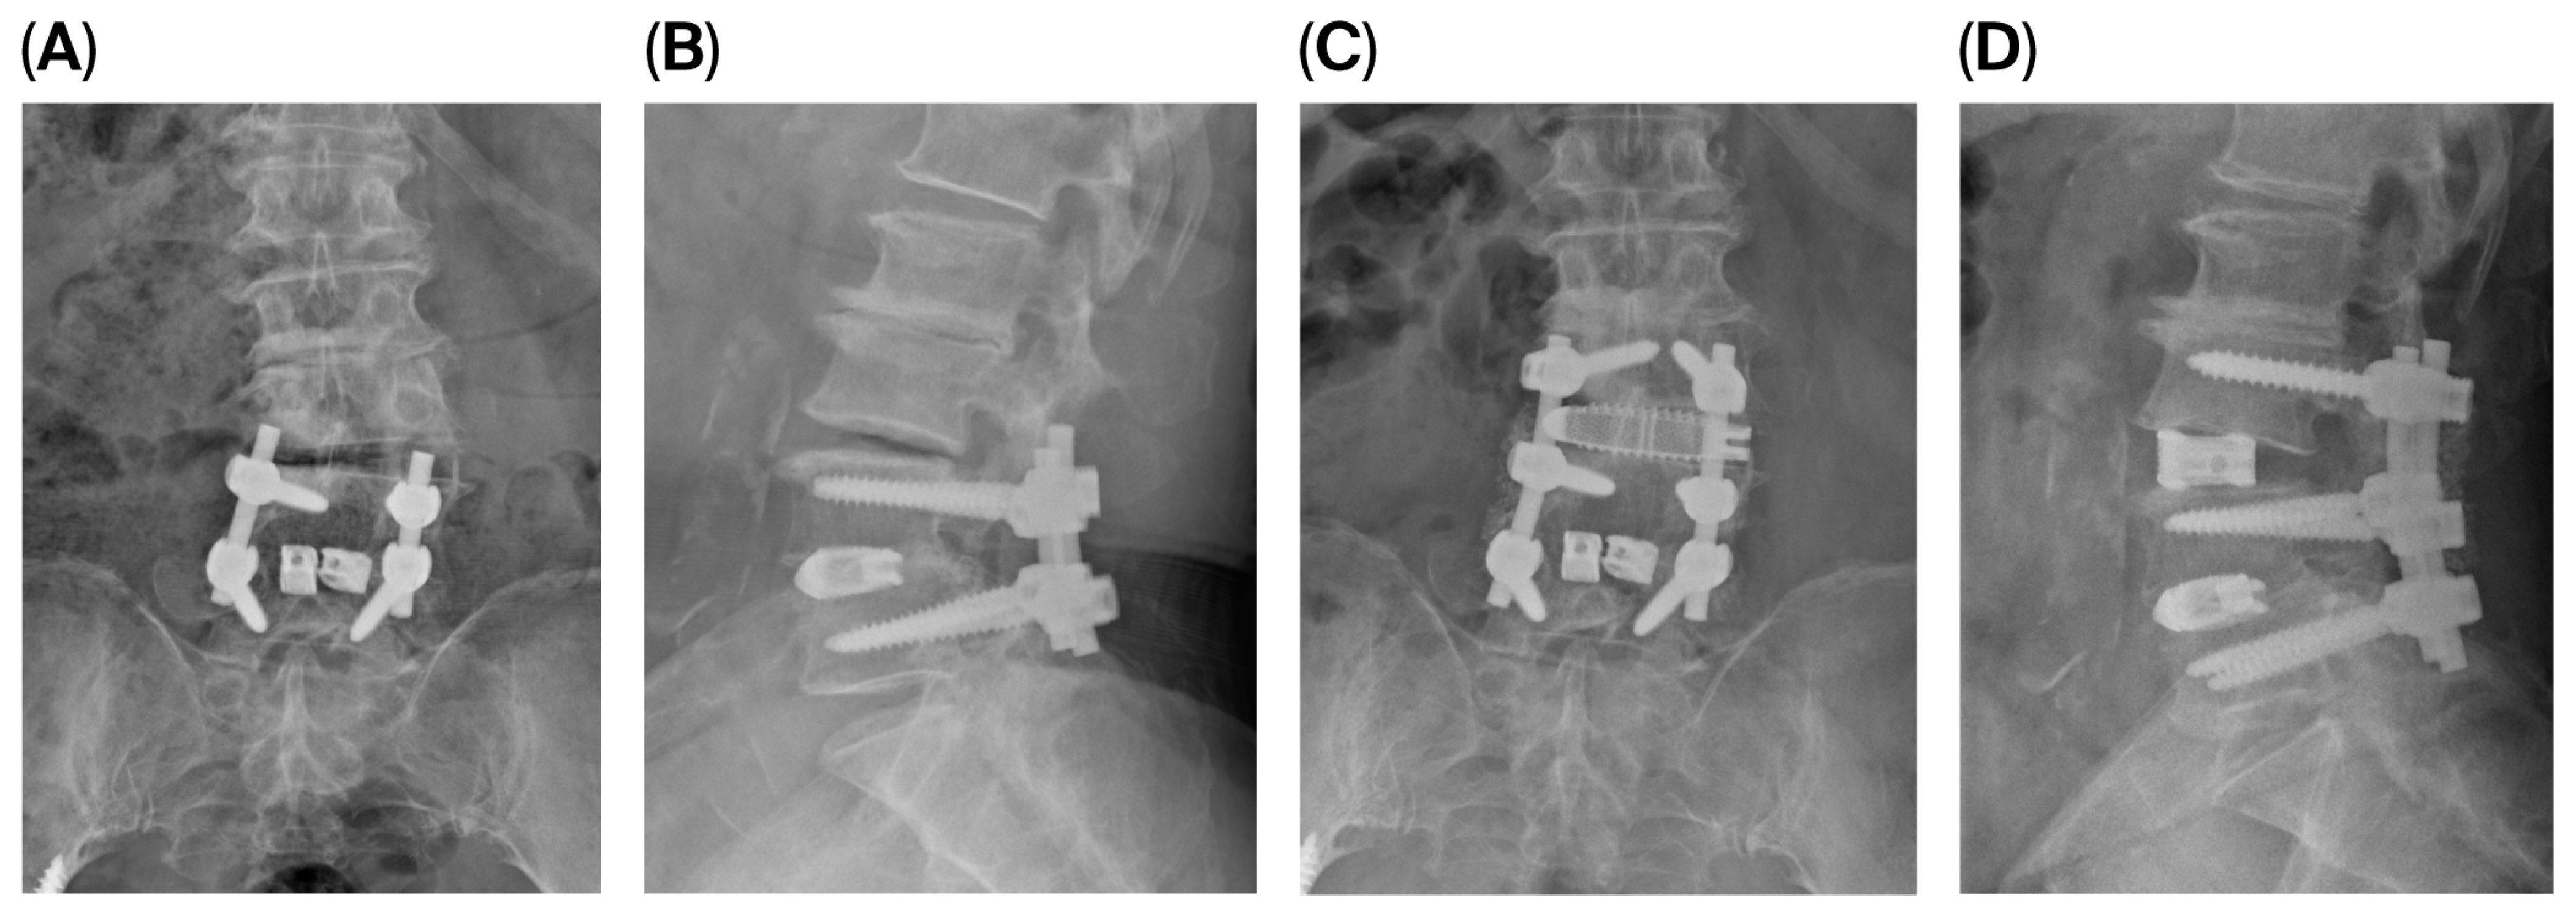

3.5. Illustrative Case